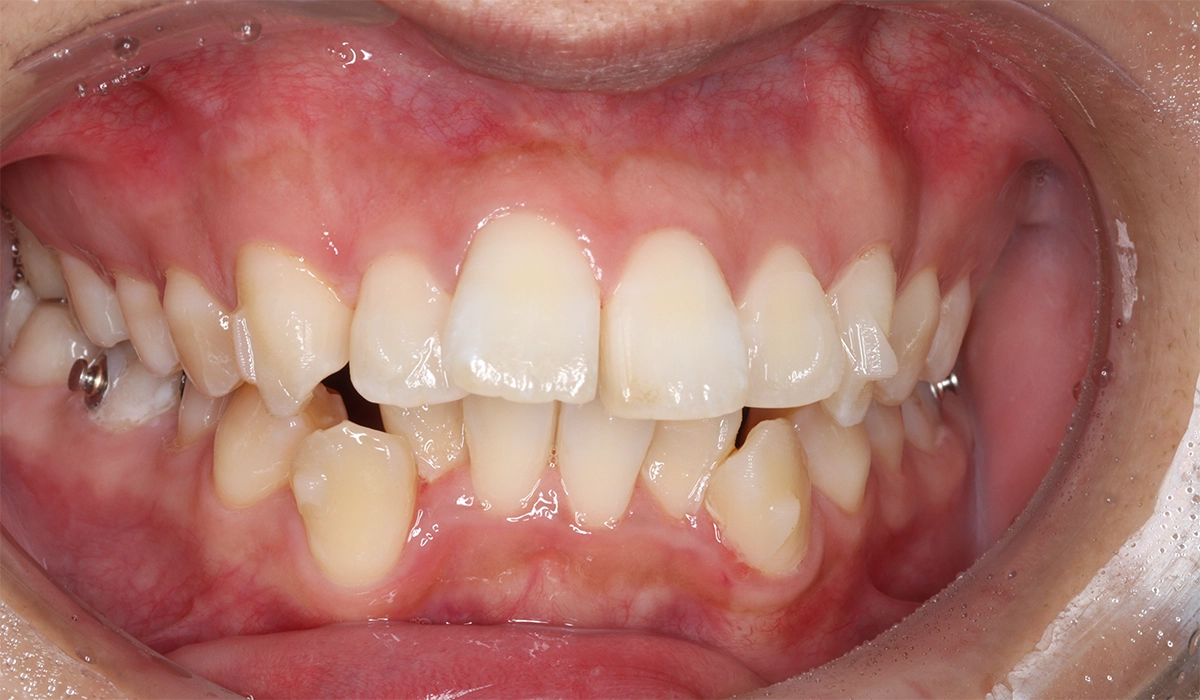

術後:正面